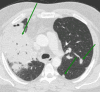

This case report depicts two patients with morbid obesity who presented to the ED with signs and symptoms of community-acquired pneumonia and were treated accordingly. Despite empiric antibiotic therapy, their symptoms did not subside, prompting further evaluation, which revealed pulmonary blastomycosis. Both patients were also found to have severe vitamin D deficiency. Treatment with amphotericin B followed by itraconazole, along with aggressive vitamin D supplementation, led to clinical improvement and resolution of lung lesions in both cases. Although blastomycosis is not rare in immunocompetent individuals, its severe forms are usually associated with underlying immunosuppression or significantly high inoculum. Blastomycosis presents a diagnostic challenge due to its nonspecific symptoms and radiographic findings. This case series underscores the importance of considering blastomycosis in the differential diagnosis of persistent pneumonia in obese individuals, particularly in endemic areas. It also suggests that vitamin D deficiency may play a role in disease susceptibility and severity. This report contributes to existing medical literature by emphasizing the potential link between obesity, vitamin D deficiency, and the risk of blastomycosis, highlighting the need for further research into this association.